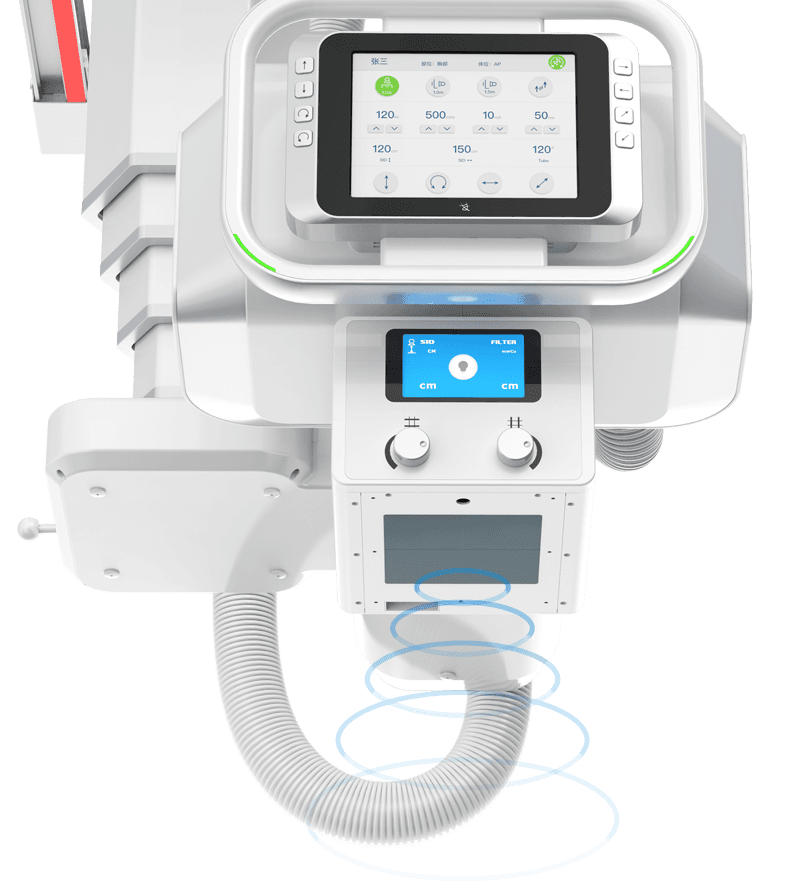

ОЮПЯТЈїШІЩЧч

Ед±ёОЮПЯТЈїШЖчЈ¬ТЈїШБйГфЈ¬Йи±ёФЛ¶Ї·ґУ¦СёЅЭЈ¬

И«іМЦ§іЦёфКТТЈїШІЩЧчЎЈ -

»ъјЬДЪЦГУпТф¶ФЅІПµНі

»ъЙнДЪЦГЧЁТµТЅУГ¶ФЅІПµНіЈ¬УпТфПµНіІЙУГёЯ±ЈХжТфР§ЙијЖЈ¬ТфЦКЗеОъєйББЎЈ

ІЩЧчТЅК¦їЙёфКТЅшРРУпТфЦёµј°ЪО»ЙгЖ¬Ј¬»јХЯФЪ»ъ·їДЪїЙЗеОъЅУКЬКТНвІЩЧчТЅК¦УпТфЦёБоЈ¬МбЙэ°ЪО»ЙгЖ¬јмІйµД°ІИ«РФУлР§ВКЎЈ